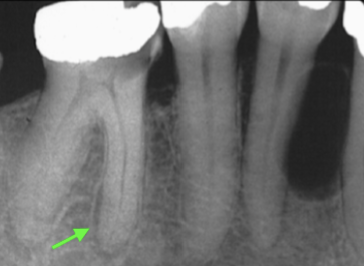

What is the Green Dot?

Submandibular Fossa

What is the Purple Dot?

Radicular Cyst